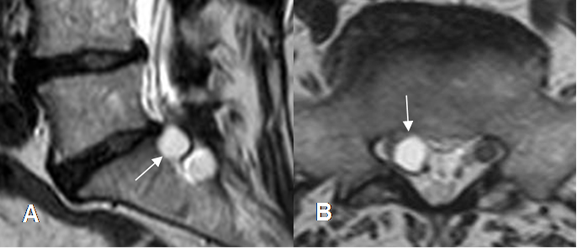

Fig 226. Quiste radicular.

A: RM sagital y B: RM axial en T2. Imagen redondeada y de consistencia líquida, a nivel paramediano derecho, que comprime las raíces.